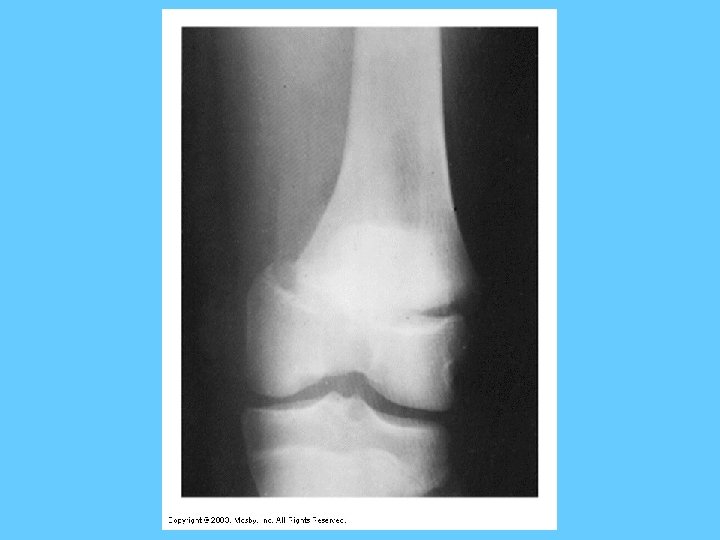

Long Bones – In More Detail • Diaphysis – Shaft of the bone – Hollow, compact bone • Epiphyses – – – Ends of the long bones Points of muscle attachment Stability to joints Spongy bone filled with red marrow Epiphyseal plate: area between diaphysis and epihyses (“growth plate”)

Endochondral Ossification (fig 7 -8 pg. 198) • 1. 2. 3. 4. 5. 6. 7. – – Bones formed from cartilage model Occurs from center to ends Typical of long bones Cartilage model Periosteum ring or collar of bone Primary ossification center and entrance of blood vessels Medullary cavity; thickening/lengthing of collar Secondary ossification center in epiphyseal cartilage Enlargement of secondary centers; bone growth moves toward diaphysis Epiphyseal plates close

Bone Growth & Resorption • Bones grow in diameter – Osteoclasts enlarge diameter of medullary cavity – Osteoblasts in the periosteum build new bone from the outside – Grow in length (at epiphyseal plates) • Childhood/adolescence – growth > resorption • Adulthood – growth = resorption • > 35 -40 yrs – growth < resorption